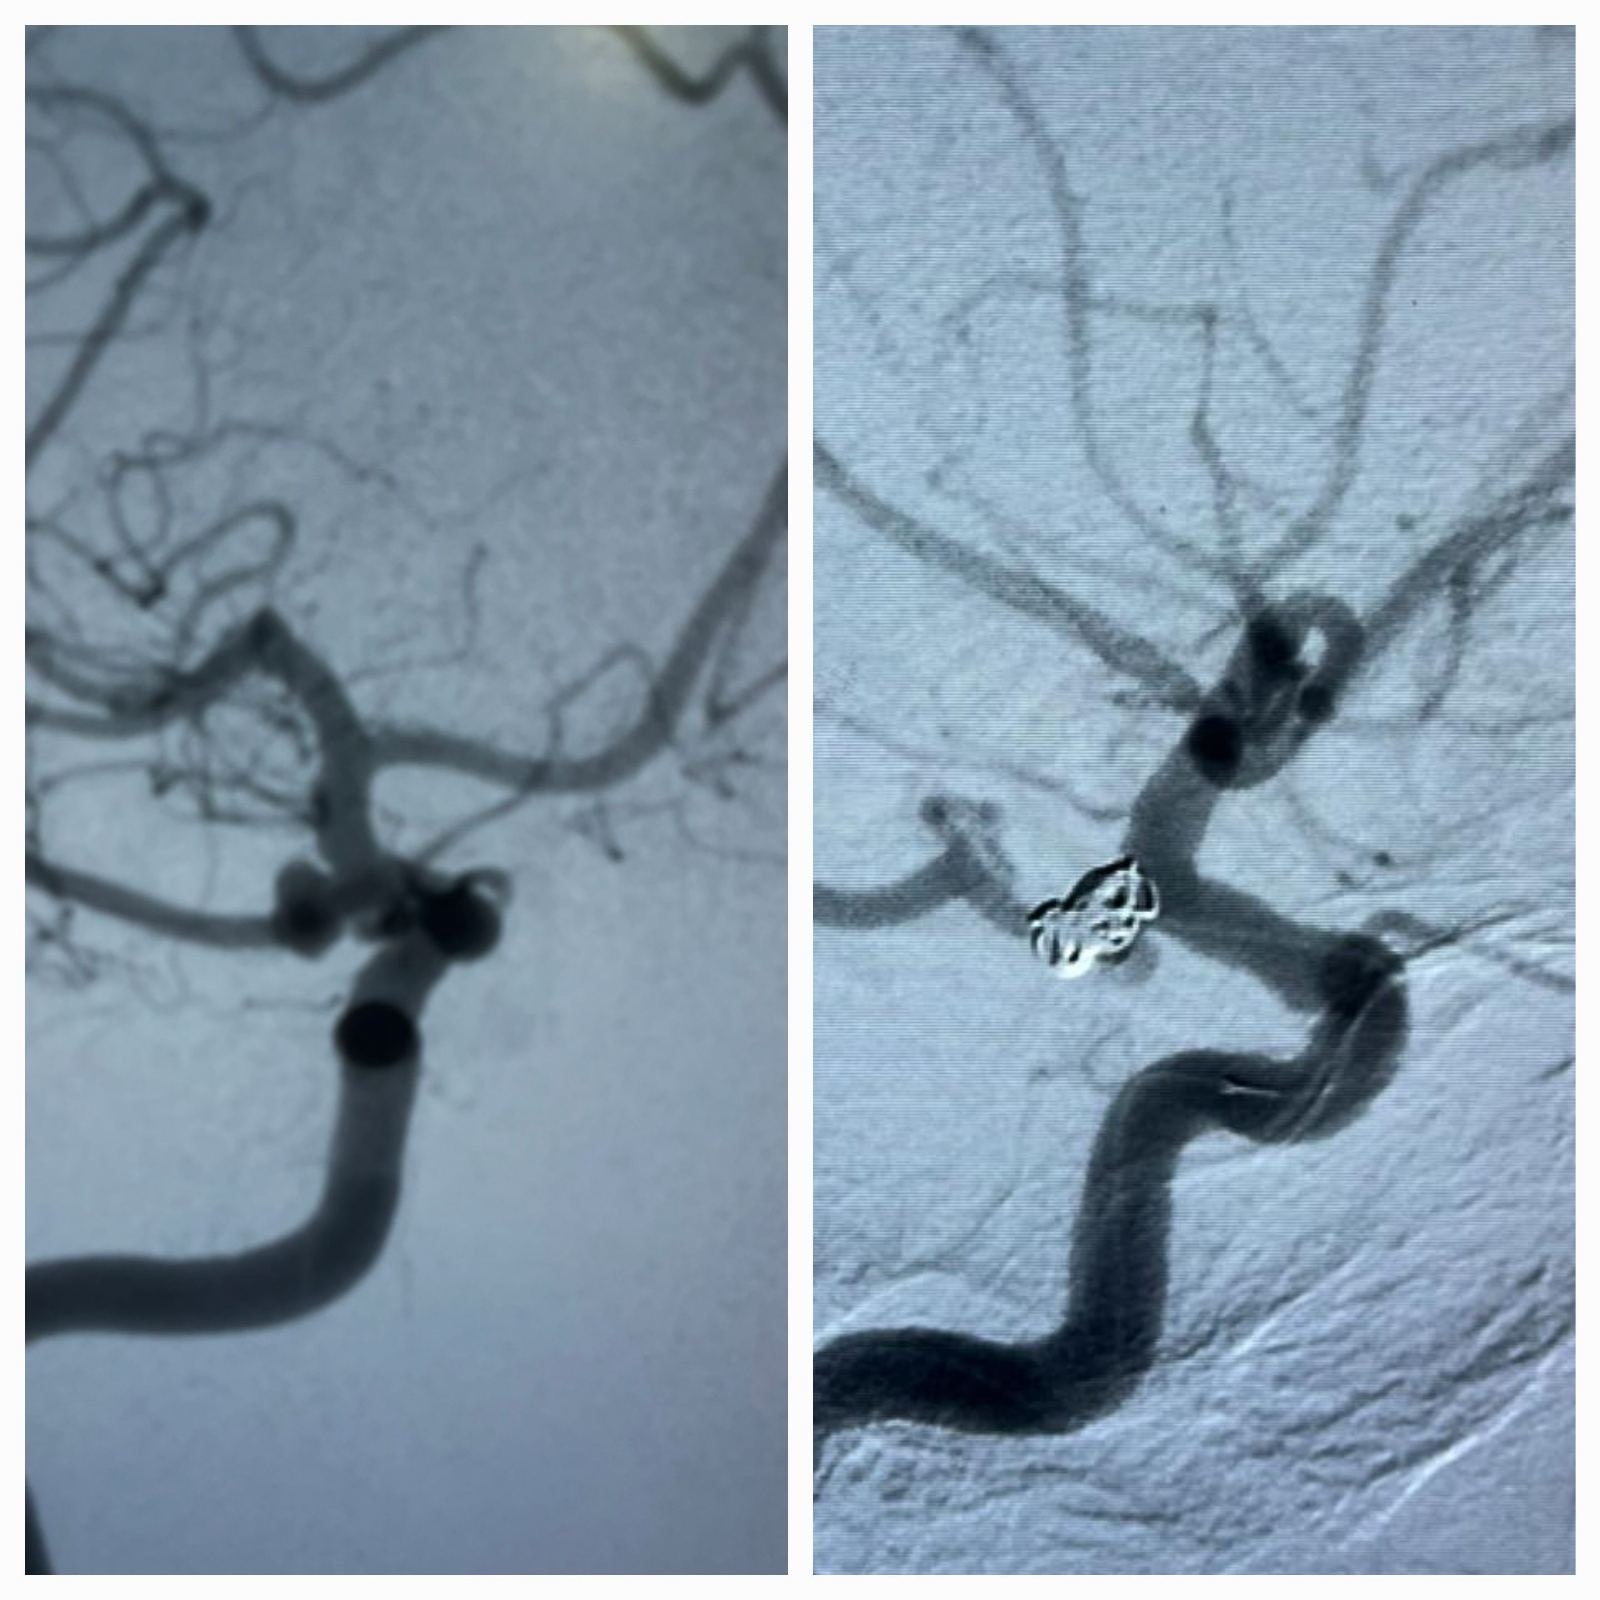

Ανεύρυσμα της πρόσθιας αναστομωτικής αρτηρίας. Εμβολισμός με ενδοσακικό stent και coils

Και η ενδαγγειακή προσεγγίση. Κατά την προσέγγιση αυτή, πλοηγούμε τα υλικά μέσα από τις αρτηρίες και τοποθετούμε μέσα στο ανεύρυσμα μεταλλικά σπειράματα (coils) μόνα ή σε συνδυασμό με ενδοπρόθεση (stent) ή τοποθετούμε ειδική κατηγορία ενδοπρόθεσης (stent) τροποιητή της ροής στην αρτηρία που φέρει το ανεύρυσμα.